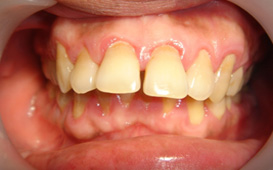

牙周病有什麼症狀 :

1. 刷牙時或不自覺的牙齦出血

2. 牙齦顏色由粉紅色變為暗紅色

3. 牙齦紅腫、疼痛甚至化膿

4. 牙齒酸軟無力;對冷熱食物敏感

5. 牙齦萎縮,齒牙慢慢移位,齒間出現間隙

6. 牙齒鬆動

7. 口臭